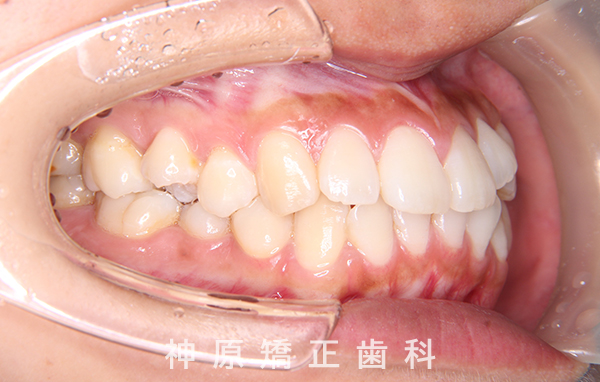

初診時

マルチブラケット装着1年後